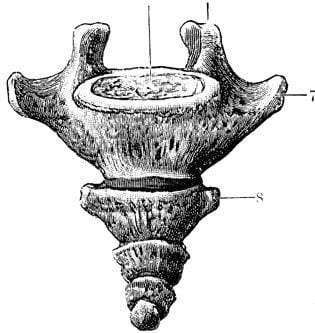

8. Coccyx

This one is better known as the tailbone and is present at the very “tail” end of the human vertebrae. We know that this is the remnant of a lost tail. Between some stages of human embryo genesis, one can actually observe a tail-like structure that is later absorbed. That fact is seriously freaky. Just imagine… if we could set up a monitor to show us the stages of embryo formation, we can actually see evolution in motion. Some scientists believe that embryogenesis is a microcosmic parallel to evolution. The coccyx is not fully useless at this point, as we do use it as a support structure while sitting.